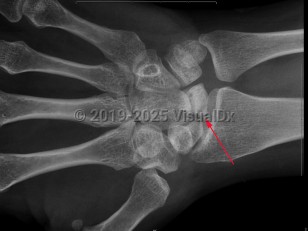

Imaging Studies image of Avascular necrosis - imageId=7924537. Click to open in gallery.  caption: '<span>Sclerosis and mild fragmentation of the lunate, compatible with Kienböck disease (avascular necrosis of the lunate).</span>'

Sclerosis and mild fragmentation of the lunate, compatible with Kienböck disease (avascular necrosis of the lunate).